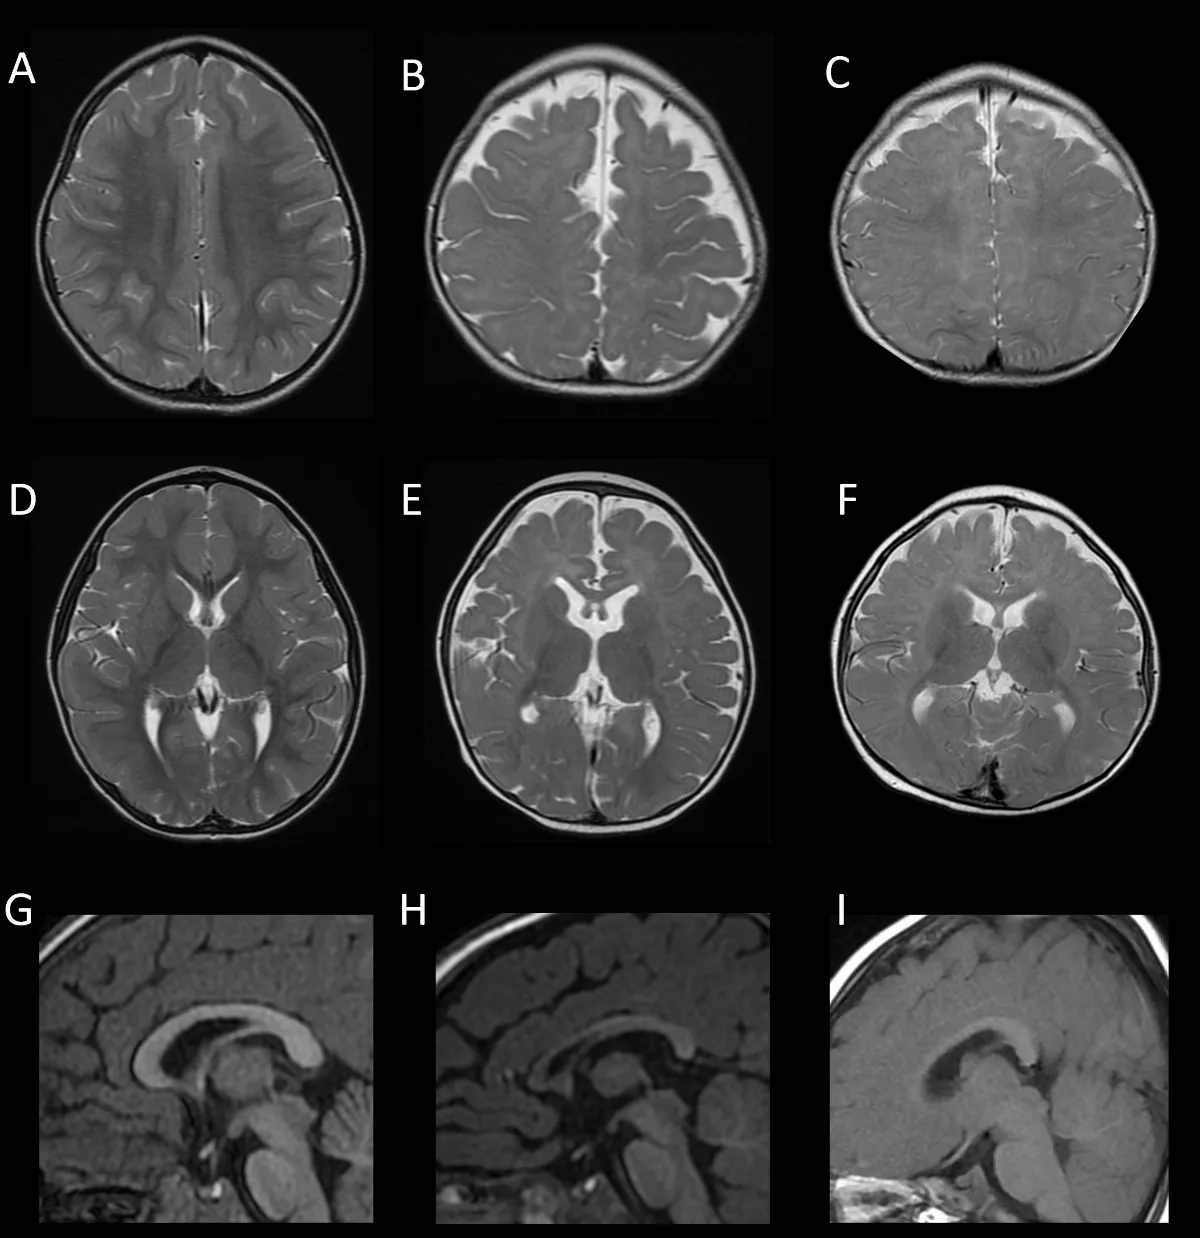

FOXG1症候群的腦部磁振造影。圖/陽明交大提供

陽明交大腦科學研究所特聘教授蔡金吾與台大兒童醫院院長李旺祚醫師,分析來自歐洲、北美、日本與台灣等國共14名FOXG1症候群患者的臨床症狀與腦部影像資料,建立一項結合實驗室功能檢測的創新流程,包含蛋白表現分析、基因調控測試與小鼠胚胎細胞遷移實驗三種方式,成功預測超過九成病患腦部異常的嚴重程度。這項突破刊登在國際權威期刊《Molecular Psychiatry》 (分子精神醫學)。